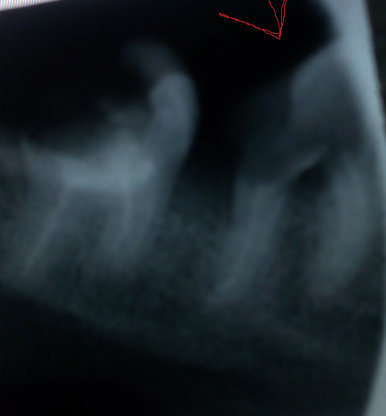

Только что во время ужина сломала передний верхний зуб! Я в панике! Сломался под корень, из десны торчит миллиметр всего, что осталось. Этот зуб (вместе с соседним) мне два года назад облагораживали — ставили фотополимеры. Благодаря этому как раз эти два передних зуба были ровные и красивые. А теперь я в панике!

Что будет делать стоматолог? Ставить коронку? Или штифт? А можно ли приклеить выпавший зуб? Или нарастить?

Наращивать зуб, ставить штифт — это все совершенно неправильная конструкция, Вы уже в этом убедились, тем более сейчас уже не на что это все крепить.

Если Вам дорого Ваше здоровье и Ваш зуб то, вам необходимо обратиться к стоматологу-ортопеду для восстановления данного зуба восстановительной культевой вкладкой, а затем установить коронку. Про восстановление пломбой и штифтом можете забыть, и помните, даже если какой-нибудь «врач» решит это сделать, Вы рискуете вовсе потерять зуб. Запомните эти мои слова!

Правда необходимо еще внимательно все осмотреть, есть вероятность потери зуба (при разрушении ниже десны).